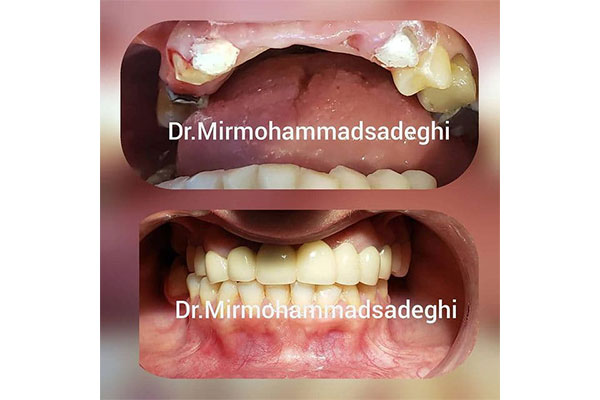

دندانپزشکی دکتر بهروز فارسی

- خدمات ایمپلنت دندان:

- مرکز تخصصی زیبایی و ایمپلنت های دندانی

- طرح لبخند

- ترمیم های زیبایی دندان

آدرس: خیابان شریعتی، ابتدای خیابان ظفر، نبش کوچه صبر، پلاک ۱، واحد ۱

تلفن: 22269850